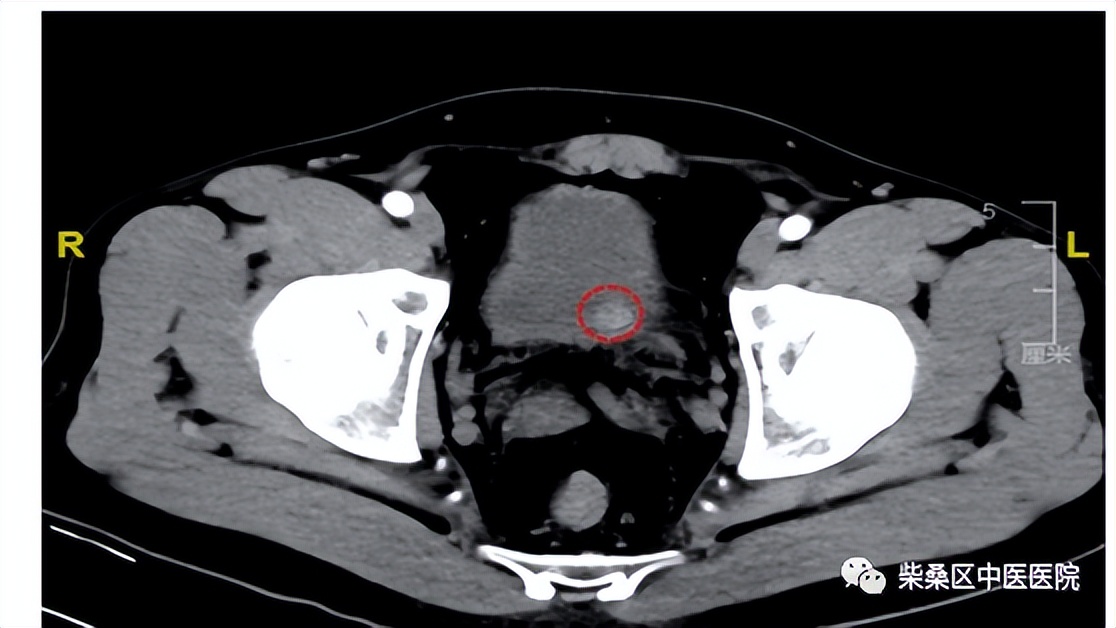

对于盆腔CT检查的患者需要憋尿。盆腔CT主要看膀胱、女性子宫、附件、直肠等。男性除膀胱以外,还需要看前列腺、直肠等。需要憋尿原因,主要是看膀胱内部结构,膀胱不充盈无法看清内部结构。

适当的憋尿,有利于将膀胱充盈起来,从而更好地观察到膀胱大小、形态、膀胱壁厚度,有没有病变及病变形态、大小、密度等情况。

正常膀胱充盈可见水样密度影,还可以看见膀胱壁薄厚,正常充盈时,膀胱壁约5mm。例如膀胱有肿瘤、结石以及膀胱憩室等疾病时都需要在膀胱充盈状态时才会显示。另外在女性盆腔CT的检查中,充盈饱满的膀胱可以与子宫附件囊肿进行有效区分。